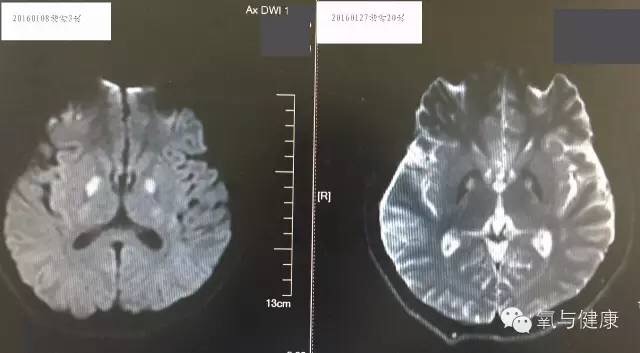

治疗经过:患者来院后完善检查,急诊予能量合剂、抗感染、保肝治疗及对症支持治疗,控制输液量及速度,防止心衰。积极对症治疗同时,2小时内急诊高压氧治疗。患者经过高压氧治疗后神志好转,但躁动明显,并出现双手震颤,结合头CT,考虑患者出现一氧化碳中毒脑病(无“假愈期”,影像表现为主要为底节区神经元损伤而非脱髓鞘改变,故考虑为一氧化碳中毒脑病而非迟发脑病),临时予以镇静,并予银杏叶制剂。高压氧治疗5次后,患者完全清醒,躁动消失,对答如常人,左手大鱼际水泡结痂,肝功、心激酶逐渐好转,仍有双手震颤,转回当地继续高压氧治疗。